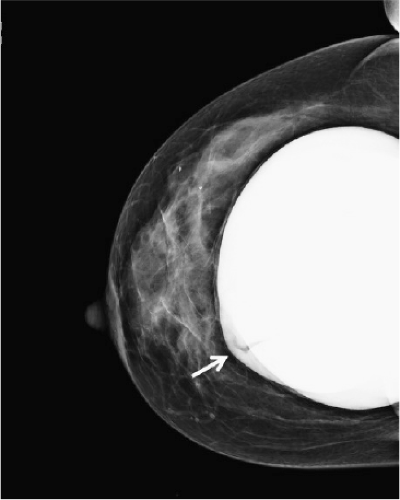

A significant number of augmented patients develop capsular contracture. Ordinarily contracture does not interfere with palpation of breast tissue, but occasionally the capsule tears, allowing part of the implant to herniate into adjacent parenchyma; this may result in a palpable (or even visible) mass within the breast (Fig. 15-1). Typically, such a palpable bulge or “knuckle” of the implant is not confusing to plastic surgeons. However, primary care physicians, gynecologists, and nurse practitioners may not be familiar with these findings; when such an abnormal mass is identified, it needs to be differentiated from a pathologic lesion. Calcification of the capsule sometimes occurs, and rigid calcium deposits may be palpated immediately adjacent to the implant. These benign calcifications must be distinguished on both physical examination and mammography from malignant microcalcifications (Fig. 15-2A,B).

One of the recognized complications of silicone gel implants is leakage of filler material, from either gel bleed or frank rupture of the elastomeric shell. When silicone gel leaks from the implant, it may elicit an inflammatory foreign body reaction, leading to fibrosis and sometimes formation of siliconomas. These abnormalities may be palpable adjacent to the implant or in other areas of the breast or chest wall (Fig. 15-3), depending upon where the silicone migrates. Siliconomas typically present as firm, discrete lumps and must be differentiated from other pathologic masses. If a silicone implant ruptures and there is spread of silicone into the breast parenchyma or adjacent structures (extracapsular rupture), it is readily apparent on mammograms (Fig. 15-4). When the silicone gel leaking from the implant remains intracapsular, it may be difficult or impossible to detect on physical examination (silent rupture). This is especially true with newer-generation, more highly cohesive gel-filled implants. Intracapsular rupture can sometimes be diagnosed on mammography (Fig. 15-5) and can reliably be imaged by magnetic resonance imaging (MRI).